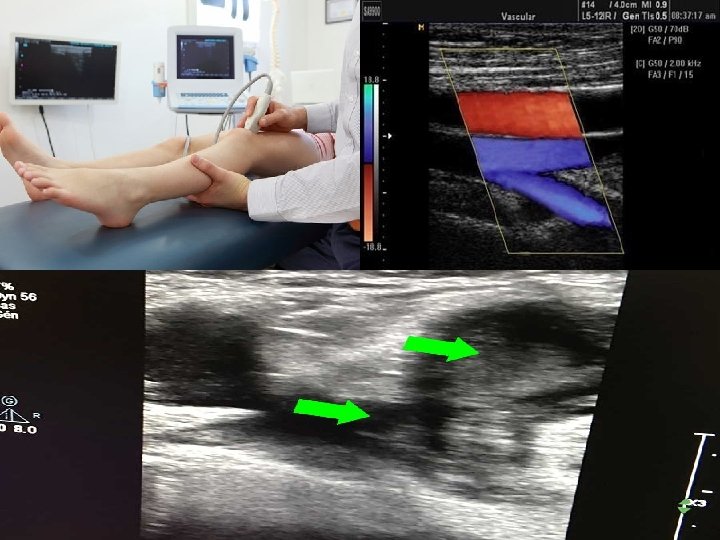

phlébographie � La phlébographie est un examen radiologique des veines après injection d’un produit de contraste iodé. -Elle concerne le plus souvent les membres inférieurs. Cet examen est effectué pour détecter un caillot dans les veines profondes

� Pour réaliser cet examen, on utilise la radioscopie et la radiographie standard. �Quand l’examen concerne le veine cave inferieure: c’est la cavographie

�on commence l’injection du produit iodé toute en suivant la progression du liquide dans les veines du membre à l’aide de la radioscopie �Lorsque la coloration des veines est adéquate, on demande au technicien de prendre des radiographies. �De nos jours, la phlébographie est effectuée beaucoup plus rarement car le doppler veineux (échographie) la remplace avantageusement pour la plupart des indications